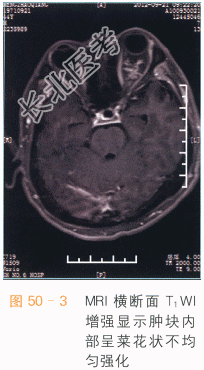

眼眶海绵状血管瘤CT表现为肌锥内类圆形边界清楚之占位,软组织密度,可见结节状钙化,注入造影剂后,呈渐进性强化,为该病的特征表现。肿块占位效应较轻,肿块较大时眼外肌受压向外侧移位,眼球向前方突出。MRI检查时,病灶的T₁WI信号和肌肉类似如图50-1所示,若有血栓形成,可表现为不规则高信号,T₂WI呈类圆形高信号,内偶可见细小低信号分隔,周围假包膜呈低信号,通常没有囊变或坏死如图50-2所示。MRI多平面扫描可以清晰显示肿块的边界,其与视神经、眼球、眼外肌分界清楚,见渐进性强化如图50-3、图50-4所示。